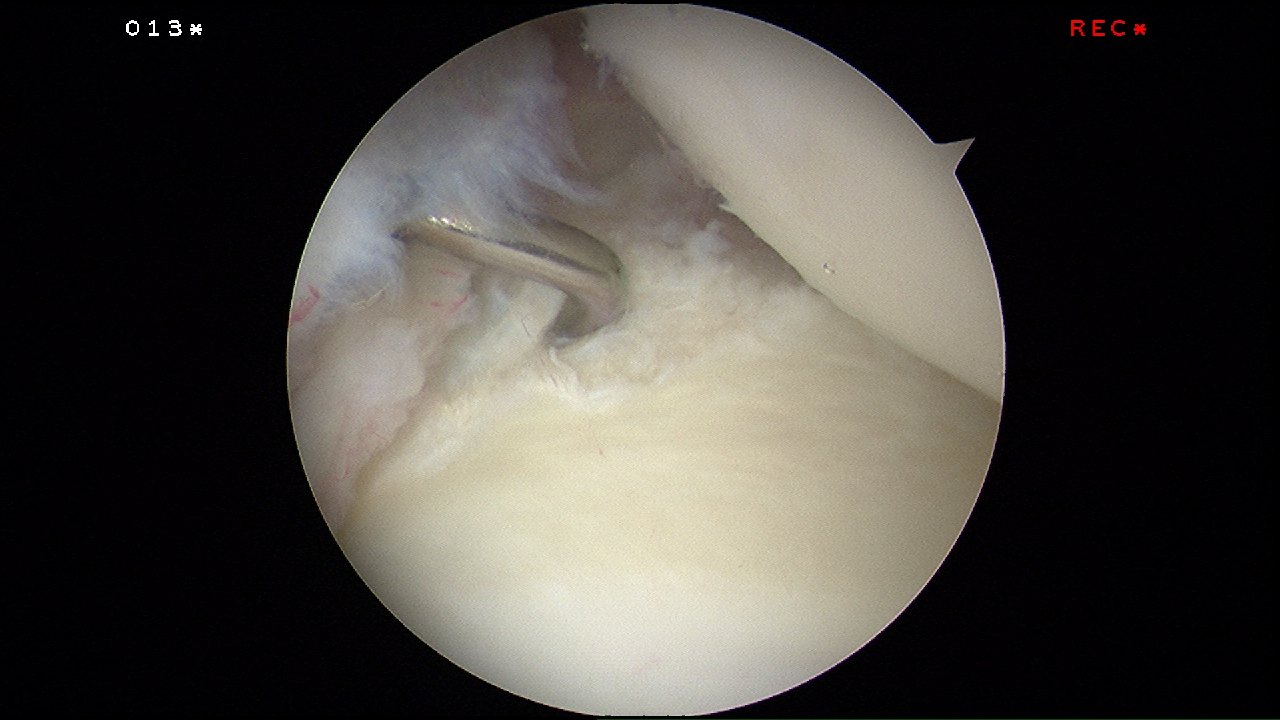

During key-hole surgery to his left shoulder, a tear in the posterior inferior glenoid labrum could be seen. This was the cause of his persistent vague shoulder pain.

The tear was delineated with an arthroscopic liberator and rasp.